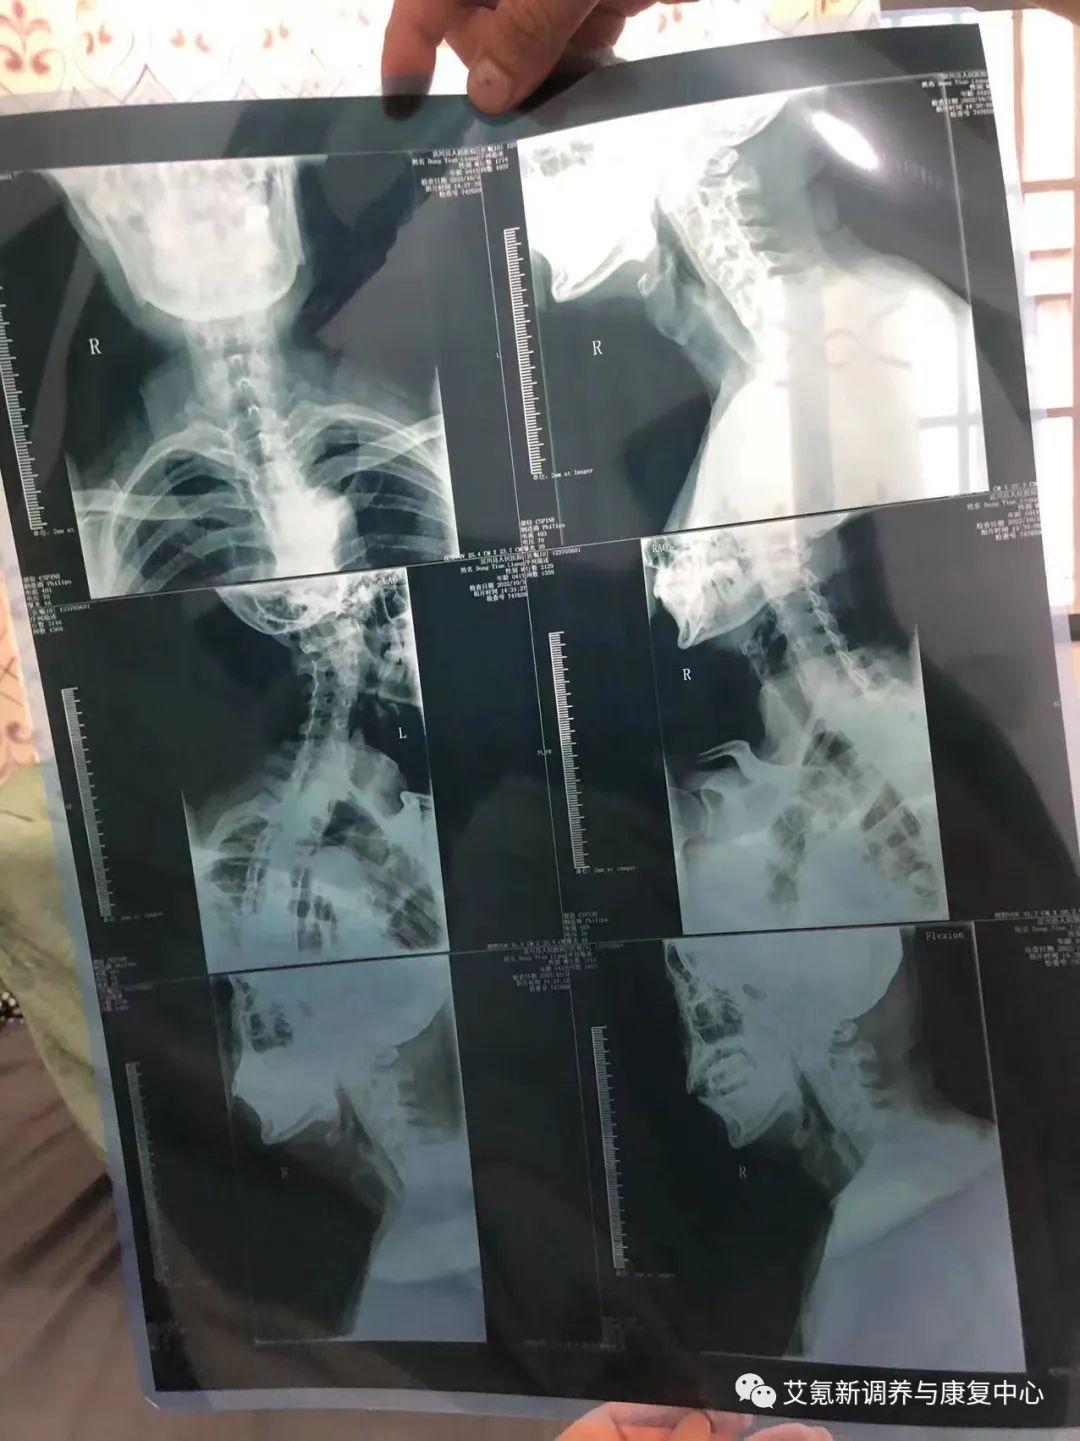

2022年10月5日诊断及拍片报告

在舒沨堂接受治疗